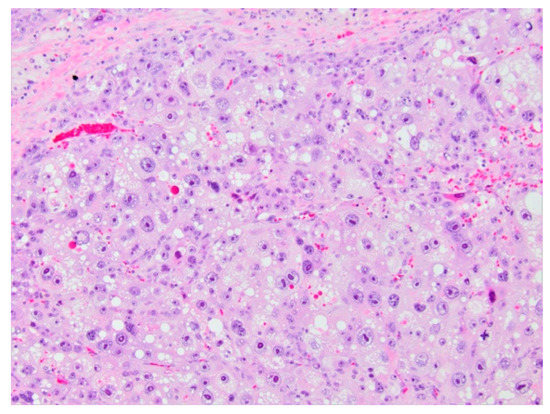

5.1.5. Histopathology and Immunohistochemistry